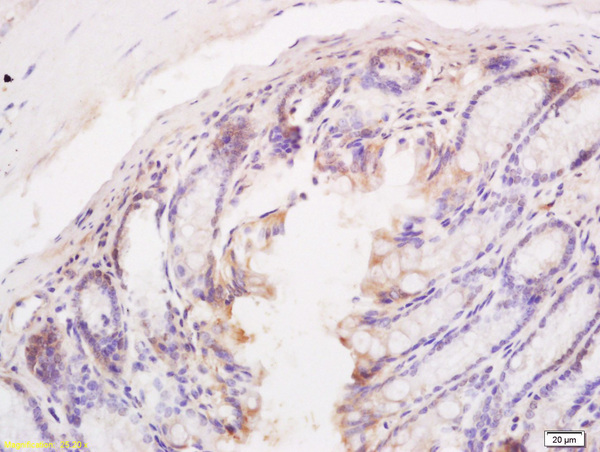

- Main image

- Experimental details

- Formalin-fixed and paraffin embedded mouse intestine tissue labeled with Anti BIM/BCL2L11 Polyclonal Antibody, Unconjugated (bs-1488R) at 1:200 followed by conjugation to the secondary antibody and DAB staining

- Sample type

- Mouse

- Other comments

- Intestine